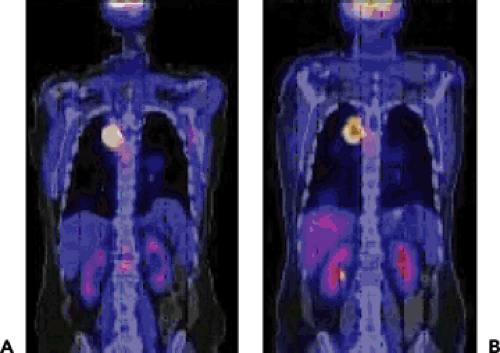

![[ 18 F]Fluciclatide PET/CT images of a right kidney tumor (arrows) in ...](https://www.researchgate.net/publication/263475425/figure/fig3/AS:512809851158528@1499274804097/18-FFluciclatide-PET-CT-images-of-a-right-kidney-tumor-arrows-in-patient-10-Axial.png)